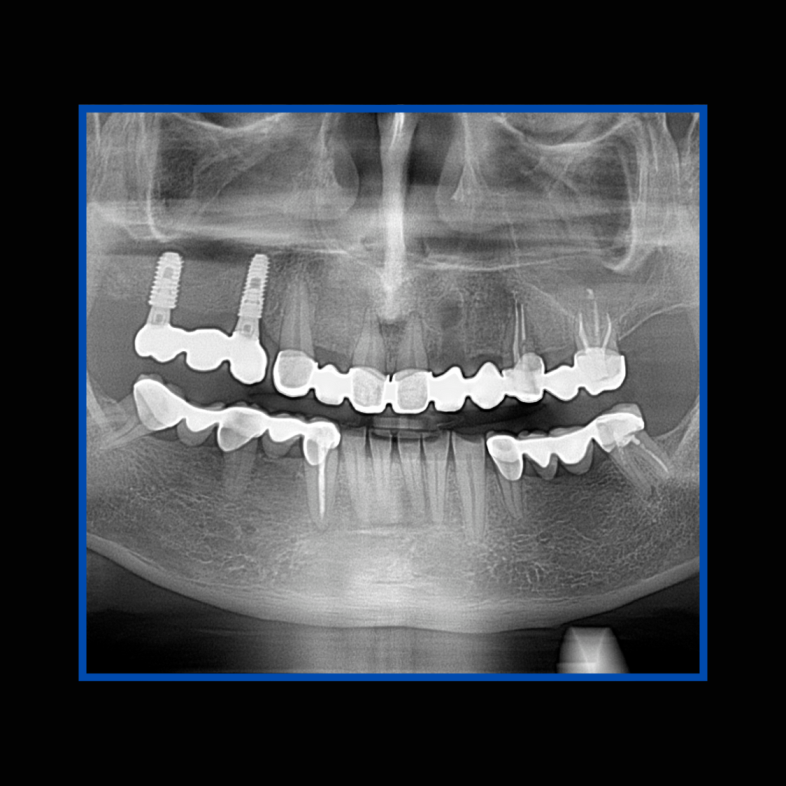

İmplant etrafındaki kemik açıklığını kemik grefti ile tedavi ettiğimiz vakamız